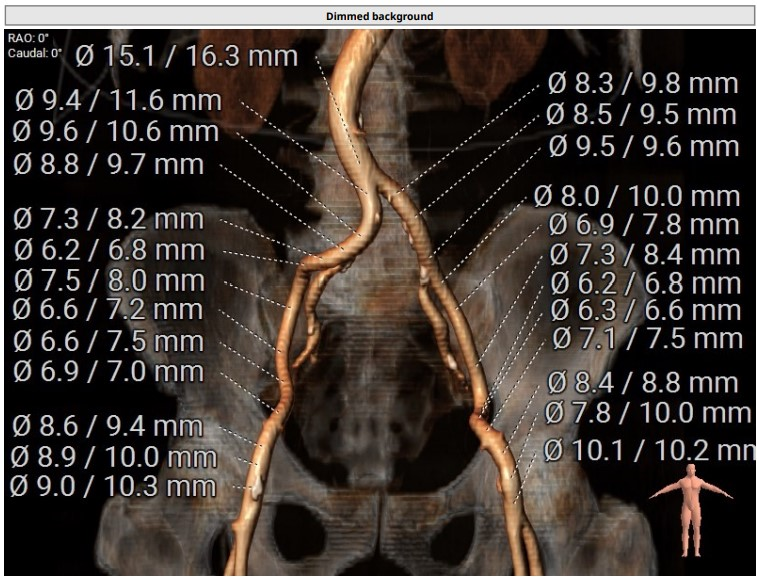

下肢入路尚可,右股动脉前壁钙化团块

主入路:左股动脉,股骨头中点以上,20F APT动脉鞘。

辅入路:右股动脉,股骨头上1/3以上。